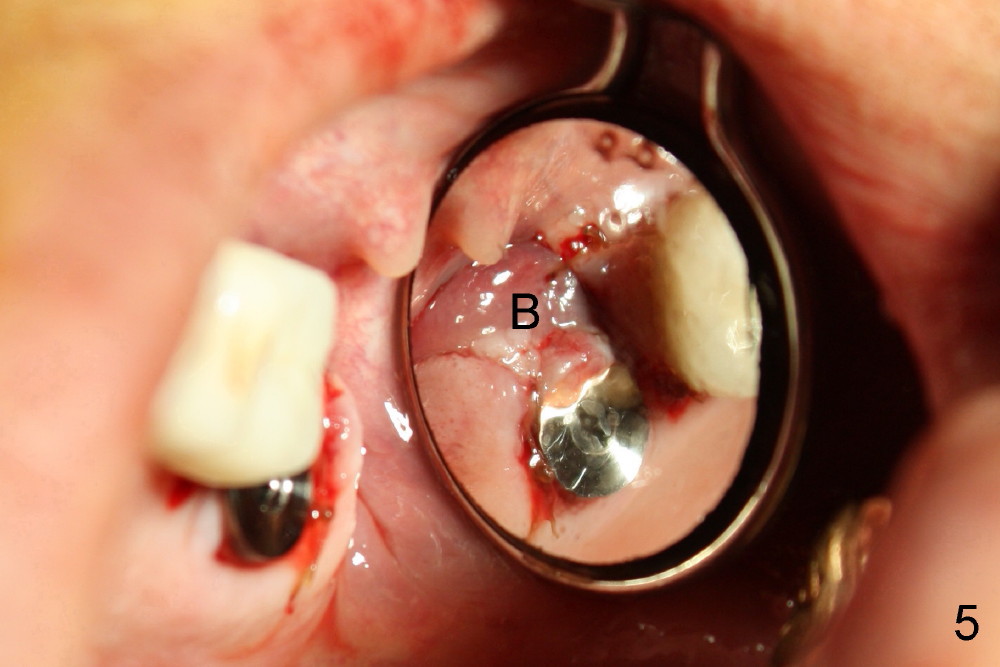

上颌磨牙有三个牙根,拔牙后一般有三个牙槽窝(图七(示意图)A:MB:近中颊侧;DB:远中颊侧;P:鄂侧),三个牙槽窝之间便是中隔(S)。如果中隔上面上颌窦不低,种植体应该种在中隔中。翁先生左上第二磨牙(图一:7)就与上颌窦无关,似乎后者不存在,前者牙根折裂,拔除后发现中隔鄂侧是一个斜坡,不容易插入圆骨凿或者钻头,所以用扁骨凿(图二)将中隔沿颊鄂侧劈开(图三),然后容易在中隔当中插入圆骨凿(图三插图白圆圈;图七B:蓝圆圈),由于中隔鄂侧阻力小,最后植牙(图七C:粉红色圆圈)不由自主地掉入鄂侧(图四),不得不移动颊侧粘骨膜瓣(图五B)关闭颊侧牙槽窝(图四插图(镜影观):MB;DB),图六镜影观(术后七天)显示种植体明显偏向鄂侧(P),可能造成以后修复困难。